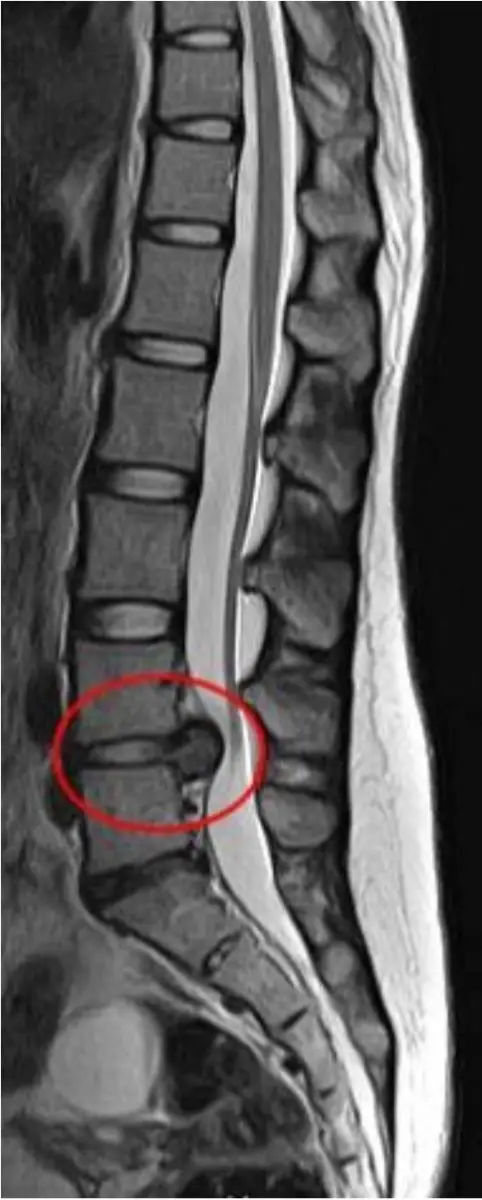

黃先生 43 歲,因為彎腰搬重物,導致嚴重下背疼痛,且其疼痛由左側臀部往下延伸至左側小腿,尤其前外側部分像針刺的麻痛感更為明顯,理學檢查發現左側足背背曲(dorsiflexion)的力量明顯比右邊弱,黃先生的核磁共振如圖所示,診斷為腰椎椎間盤突出,最可能壓迫的神經為何?

核磁共振矢狀面顯示 L4 – L5 椎間盤向後外側突出。腰椎神經根走行規則為「椎間盤往上壓隔壁、往下壓自己」,亦即:

• L4 – L5 椎間盤突出→最常壓迫通過該層椎間盤後方的「下行 (traversing) L5 nerve root」。

C. L5:症狀典型——外側小腿與足背麻痛、足背屈無力;與 L4 – L5 disc herniation 的壓迫對象完全吻合。